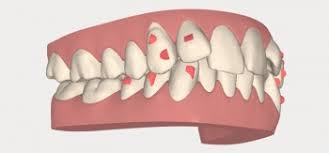

Apiñamiento dental inferior propio de los años: ¿tiene solución?

Apiñamiento dental y ortodoncia Con el paso del tiempo es normal que los dientes se muevan, lo que puede provocar un apiñamiento dental. Este trastorno se […]